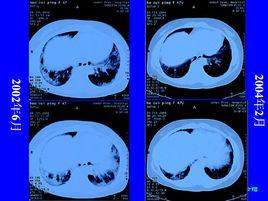

影像學特點:胸部X線片主要表現是在兩肺基底部和周邊部的網狀陰影,常為雙側、不對稱性,伴有肺容積減少。CT對UIP的診斷具有重要的意義,主要表現為兩肺片狀、以基底部為主的網狀陰影,可有少量毛玻璃狀影。在纖維化嚴重的區域,常有牽引性支氣管和細支氣管擴張,和(或)胸膜下的蜂窩樣改變。